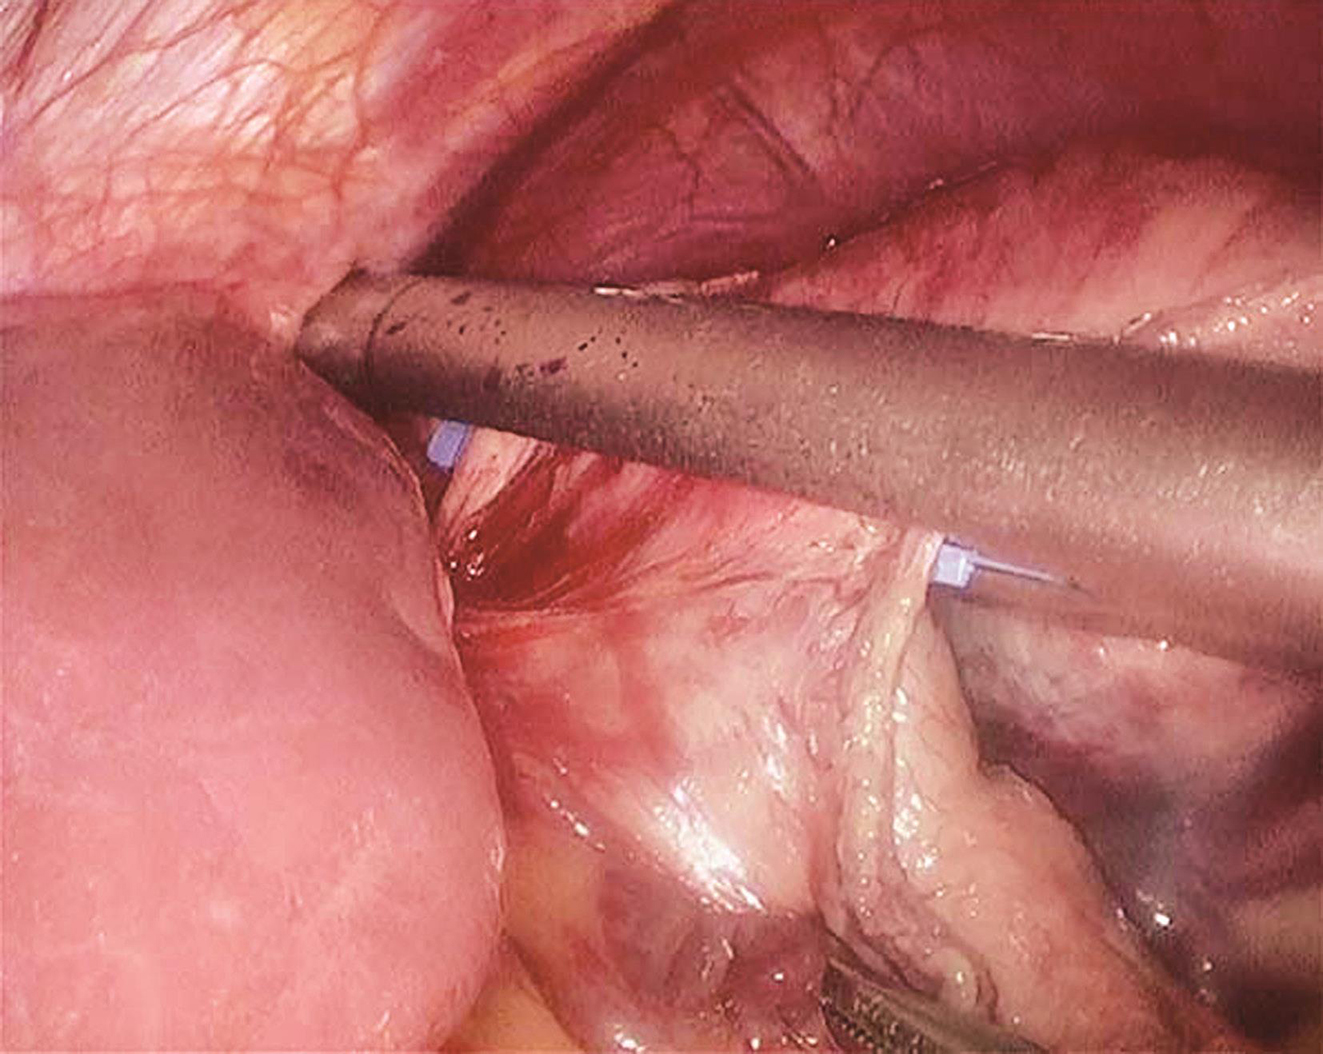

患者于2018年10月17日行腹腔镜下胃肿瘤切除术+胆囊切除术,术中见胆囊大小约7cm×5cm×3cm,胆囊壁糙,胆囊内含混合型结石3枚,直径均1cm左右,胆总管不扩张。胃体上部大弯侧直径5cm肿瘤,向胃腔内外突出,起自黏膜下,胃周淋巴结无肿大,术中充分游离胃体上部及胃底后,以切割吻合器完成肿瘤切除(图2),切除后标本及时置入标本袋中,经脐部戳孔延长后取出。

图2 腹腔镜下以腔内直线切割吻合器完成肿瘤切除